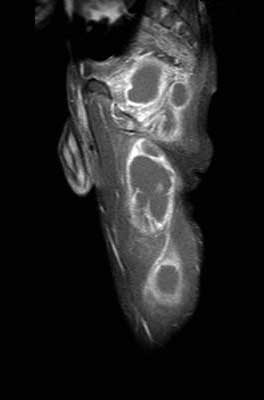

Просмотрел все предоставленные исследовании и первый МРТ снимок показывает, что ни псоас и не прямая кишка не вовлечены в процесс. Медиальнее от псоас слева имеется абцесс идущий сверху. На втором боковом изображении белое пятно это сердце, потому что находится выше диафрагмы. Спереди передная стенка, а пятно сзади это начало абцесса.Третий и четвертые снимки показывают уровень таза и медиально расположенный многокамеральный абцесс идущий между мышцами.

Обычный снимок позвонка давно бы снял все сомнения, а дополнительные снимки показали бы откуда идет "холодный абцесс" . А сейчась смело можно заключить: ТВС из нижних отделов торокального позвонка.